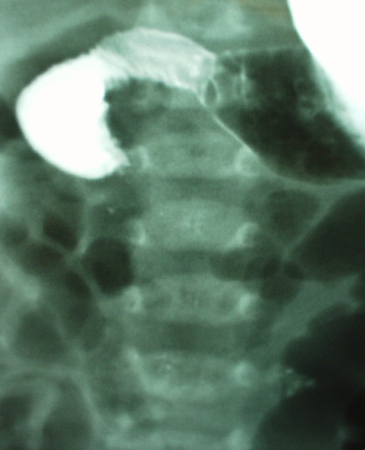

Volvo

faixa etária infantil; história de vômitos biliosos; a dor geralmente se manifesta como transição notável para um estado inconsolável

Exame físico

distensão e sensibilidade abdominais frequentemente difusas; ruídos hidroaéreos fracos ou ausentes, abdome rígido, defesa, dor à descompressão brusca, febre ou hematoquezia

Primeira investigação

- estudo do trato gastrointestinal superior com contraste:

sinal de bico de pássaro da estenose no local do volvo

Mais - radiografia abdominal:

obstrução parcial ou completa; alças intestinais dilatadas; níveis hidroaéreos; ar livre abdominal com perfuração